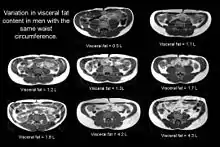

Indirect methods such as waist circumference are not suitable as individuals with an identical waist circumference can have vastly different levels of internal fat.

The figure clearly shows that despite having an identical waist circumference (in this example all men had a waist of 84 cm), there is considerable variation in the amount of visceral fat (volumes shown on the image in litres) present.